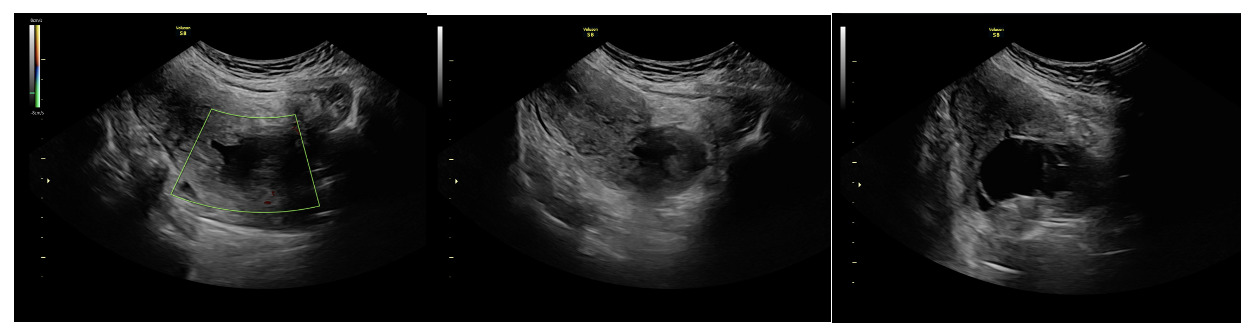

Results

A 31-year-old gravida 2 para 1001 at 13 weeks and 6 days gestation by a 7-week ultrasound presented to ULH for surgical management of a missed abortion in the setting of suspected CSP versus PAS. The patient had previously been seen at an outside hospital emergency room for concerns of bleeding and pelvic pain. Ultrasound workups for these concerns were significant for viable intrauterine pregnancy and moderate subchorionic hemorrhage superiorly, grossly measuring 5 cm at the largest dimension. Two weeks after her initial emergency department (ED) visit, the patient was seen in our practice’s general obstetric clinic. A first trimester ultrasound was performed at this time and again demonstrated a 5 cm subchorionic hemorrhage (Figure 1). At this time, concern for CSP versus PAS was also noted, and the patient was advised to return for a follow-up scan. When the patient returned for further evaluation of placental pathology, ultrasound revealed fetal demise with absent fetal cardiac activity (Figure 2). Following discussion with the maternal fetal medicine (MFM) provider, the patient ultimately elected for surgical evacuation of the products of conception to mitigate spontaneous bleeding risks in the setting of CSP versus PAS.